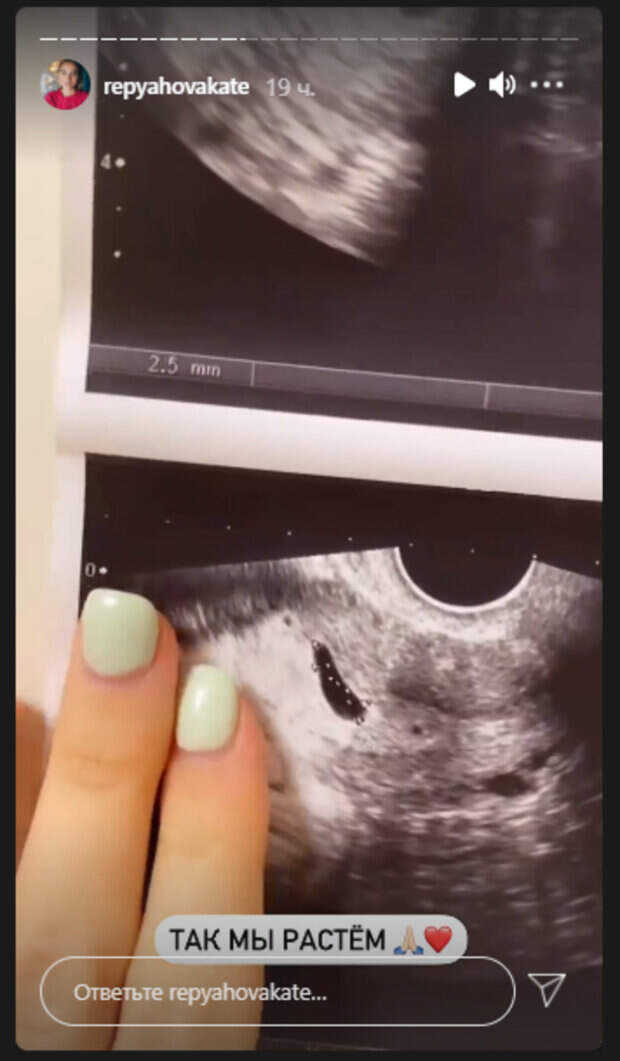

Супруга певца Виктора Павлика Екатерина Репяхова не удержалась и похвасталась своим "чудом" Девушка совсем недавно раскрыла, что находится в интересном положении, но уже активно делится фото не только своего беременного животика, но и еще нерожденного малыша. Как передает Politeka.net, 26-летняя Репяхова опубликовала свежие кадры в "сториз" в Инстаграм, на которых похвасталась первыми снимками ребенка.

"Когда-то мы были такие... Это первое наши УЗИ. Потом на 8-й недельке мы стали такими... А сейчас еще больше!", - комментировала Екатерина, гладя пальцами по фото. Девушка рассказала, что уже успела сделать четыре УЗИ. Первое - на 4 неделе, когда ей сообщении о беременности. Второе - когда становилась на учёт на 8 неделе, третье - на 12-й, и последнее, четвертое - на 16-й. До этого жена Павлика раскрыла главную интригу - срок и предполагаемую дату родов. Сейчас девушка находится на 19-й неделе беременности. Они с мужем ожидают появление малыша 13 июня. Примечательно, что именно в этот день Екатерине исполнится 27. "Я так люблю свой день рождения, так люблю начало лета, что Б-г послал мне малыша именно на этот период. Вот такой подарочек...", - делилась эмоциями будущая мама. Пол ребенка они с мужем пока держат в интриге. Ранее Репяхова рассказывала, как с беременностью изменились ее вкусы. Так, девушка стала есть больше сладкого, хотя ранее была к этому равнодушна. "Думаешь, ты потолстеешь, и никогда не выйдешь замуж больше?", - подкалывал ее Павлик. Напомним, романтичный Виктор Павлик побаловал беременную жену прямо в душе: "Неординарное начало...". Как сообщала Politeka, беременная жена Виктора Павлика рассказала о сложном диагнозе, фото из больницы: "Лекарства перестали помогать. ..". Также Politeka писала, что молодая жена Виктора Павлика показала беременный живот без одежды и раскрыла свою проблему.